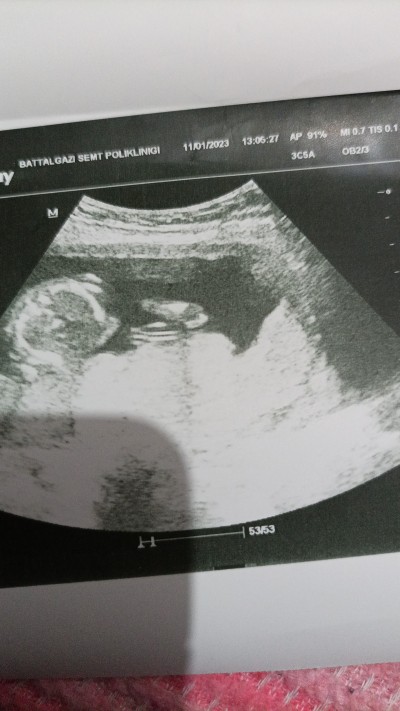

Sizce de o görünen pipi mı yoksa kordon olabilr mi ya çok merak ediyorum doktor da emin konuşmadı sadece benziyor dedi